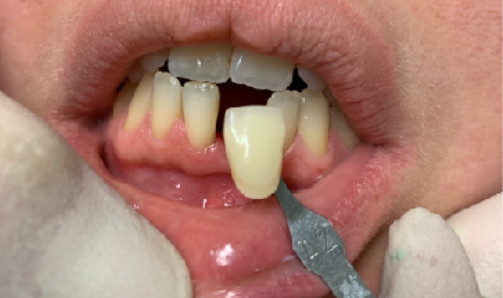

Il diametro ridotto del collo consente di mettersi al riparo da eventuali periimplantiti e migliora nettamente la velocità della guarigione. In questo caso è stato maschiato con un diametro 4 ed è stato inserito un impianto di Tramonte diametro 4 mm a 7 spire a collo corto . Il titanio utilizzato è sempre di grado 4.

| Saldatura : No | Zona dentale: incisivo inferiore 31 |

| Situazione estrattiva: Impianto postestrattivo immediato a carico immediato. | Densità secondo Misch: D2 |

| Sequenza frese: Solo fresa lanceolata | Sequenza maschiatori: maschiatore diametro 4 mm |